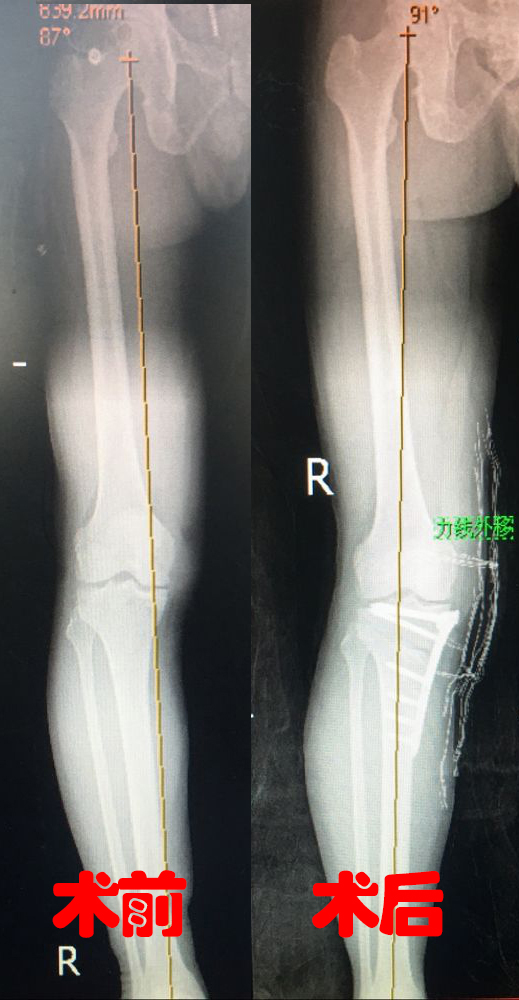

HTO 是一种保留原有关节,通过矫正膝关节负重力线,使70%的力量通过正常的膝外侧传导,从而阻止软骨进一步磨损,缓解疼痛、改善膝关节功能的保膝手术。 在徐伟敏主任的建议下,孙大叔做了胫骨近端高位截骨术,术后腿变直了,通过康复锻炼,膝关节疼痛也消失了。3个月后,孙大叔又重新下地干活了。 术前黄线(力线)在膝内侧,术后通过膝中央 对于严重的膝关节磨损、坏死,人工关节置换是最直接的一个选择。HTO是目前公认的治疗膝关节内侧间室骨性关节炎并内翻畸形的安全有效方法,能缓解疼痛、修复膝关节,提高患者生活质量,HTO手术为病人提供了保膝治疗新选择。 H T O · 优势 · 1.术后疼痛少; 2.恢复快,创伤小; 3.关节活动度更好。 · 哪些患者适合 · 1. 关节外畸形的患者; 2. 膝关节稳定性良好的患者; 3. 外侧间室关节软骨退变不明显的患者; 4. 希望术后膝关节运动功能好的患者; 5. 男性小于65岁,女性小于60岁。